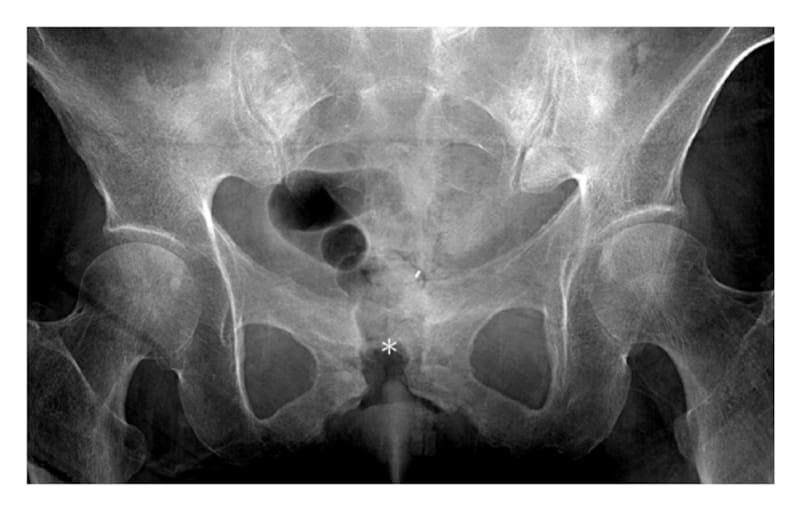

En el caso de la osteomielitis púbica, la infección se localiza en la sínfisis púbica, una articulación que, aunque no tiene el mismo movimiento que otras articulaciones móviles, soporta cargas importantes durante la marcha y otras actividades físicas.

Esta variante representa apenas un pequeño porcentaje de todas las osteomielitis y suele diagnosticarse mediante pruebas de imagen, como tomografía computarizada (TAC) o resonancia magnética, combinadas con cultivos bacterianos para identificar el agente infeccioso.